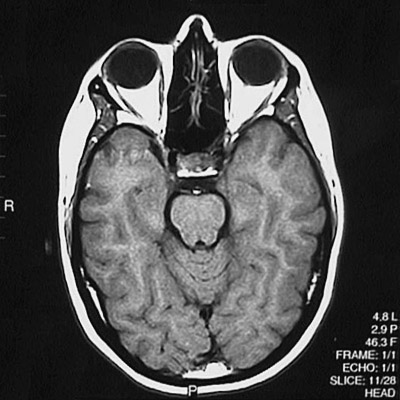

This is a normal axial T1 weighted MRI scan demonstrating the temporal lobe and occipital lobe and basis pontis and aqueduct of Sylvius and cerebellar vermis and ethmoid sinus and pituitary and orbit.